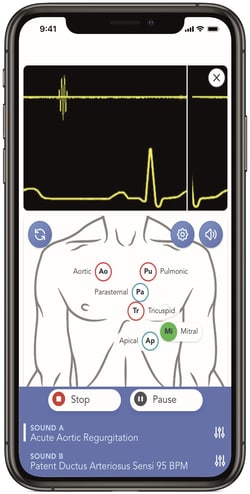

- Introducing SAM4, the latest advancement in auscultation training from Cardionics.

- SAM4 builds upon the success of its predecessors, including SAM Basic, SAM II, and SAM 3G, and brings exclusive new features to elevate the auscultation learning experience.